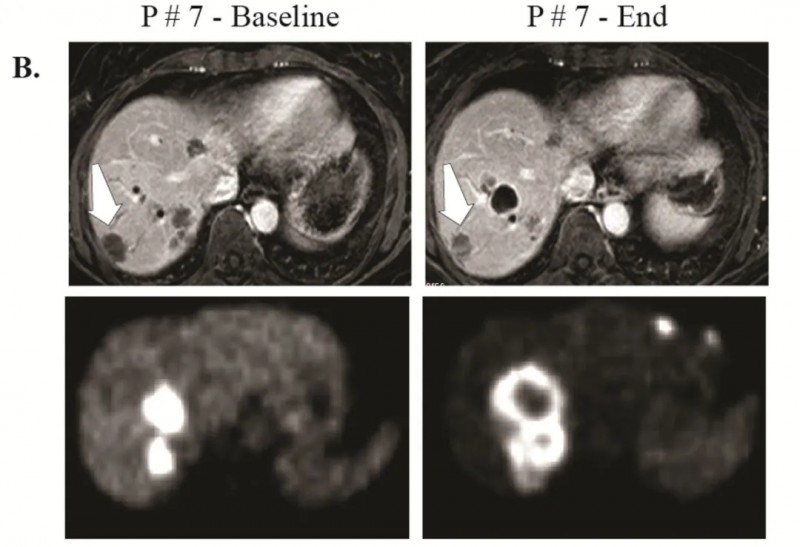

《临床癌症研究》报道的一项I期临床试验——应用CAR-T细胞肝动脉灌注治疗(HAI)CEA阳性肝转移瘤,成功验证了该疗法的可行性。